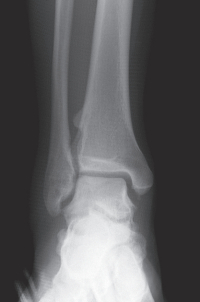

20歳の男性。右足関節の外側部痛を主訴に来院した。昨日、サッカーの練習中に右足関節を捻り受傷した。右足関節の外果周囲に皮下出血を伴う腫脹を認める。右足関節のエックス線写真と受傷肢位を強制したストレスエックス線写真を別に示す。

右足関節の状態として適切なのはどれか。

e. 不安定性